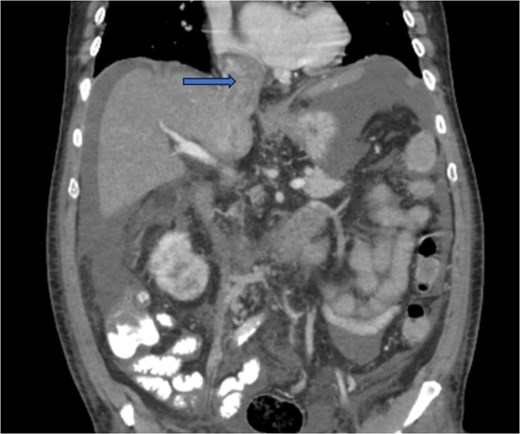

Diagnostic imaging began with a chest X-ray that indicated bilateral pleural effusions. An abdominal ultrasound detected a 4.6 × 4.2 × 4.3 cm echogenic lesion in the right hepatic lobe. Further imaging with a computed tomography (CT) scan of the chest, abdomen, and pelvis revealed a large mass originating from the posterior aspect of the right mid-kidney consistent with RCC (Fig. 1). The mass associated with thrombus extended into the renal sinus and collecting system, traveled along the right renal vein to the inferior vena cava (IVC), and projected into the right atrium (Figs 2 and 3). During hospitalization, bilateral lower extremity pain led to the diagnosis of bilateral deep vein thromboses via duplex venous ultrasound. Echocardiography showed normal left ventricular ejection fraction, impaired diastolic filling, mildly increased ventricular wall thickness, and an echogenic mass extending from the right atrium into the IVC consistent with the tumor thrombus.

CT chest abdomen and pelvis with contrast showing tumor thrombus is seen within the IVC extending over a long distance from the level of the renal vein cephalad into the right atrium.

CT chest abdomen and pelvis with contrast showing inferior extension to the level of the distal margin of the IVC.